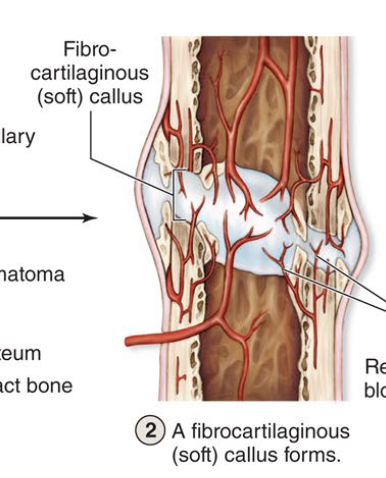

Fibrocartilagenous Callus Forms

Second step to fracture repair (take at least 3 weeks)

Soft callus of collagen & cartilage bridge the broken bone